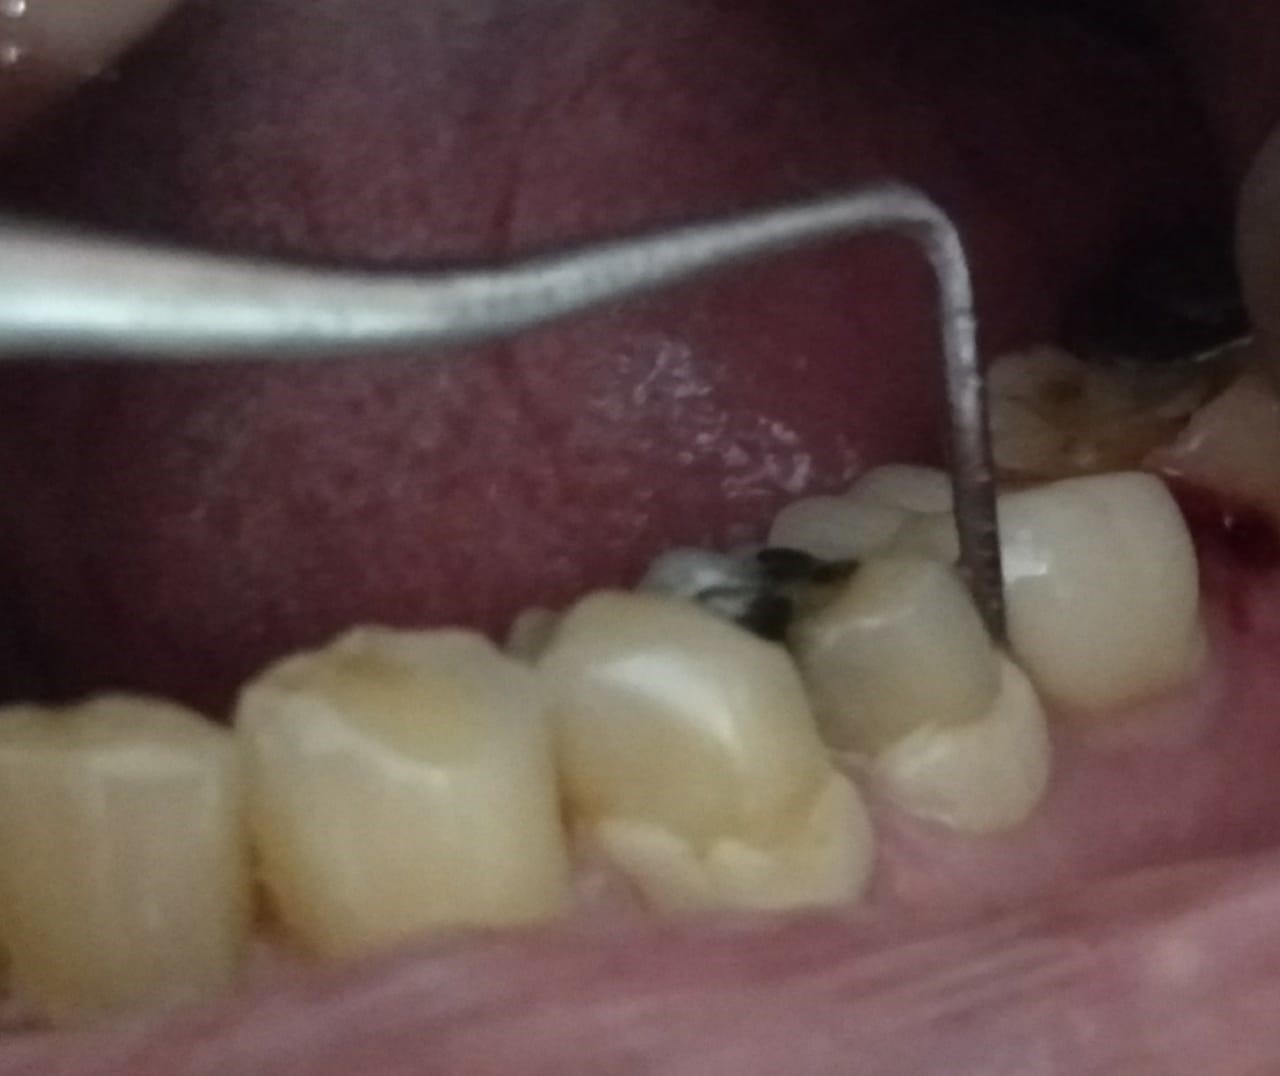

Case Study: A 65-year-old female patient came to the dental operatory with gingival inflammation and bleeding around tooth no 36.

Laser assisted peri-implantitis treatment around tooth no 36.